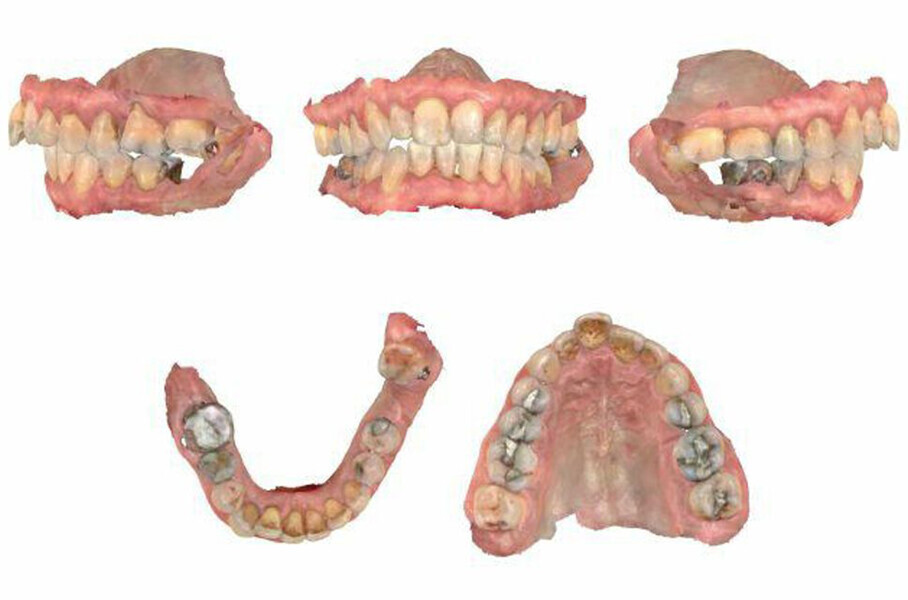

The periodontal treatment of an adult patient undergoing treatment with aligners is illustrated in demonstration of these points. Orthodontic planning considered the extra-oral photographs (Fig. 1) and intra-oral photographs (Figs. 2 & 3). Intra-oral scanning (Fig. 4) and radiographic documentation using panoramic radiographs and cephalometric radiographs (Figs. 5 & 6) were also carried out. From a periodontal perspective, periapical radiographs were recommended (Fig. 7), as this was an adult patient who smoked and showed clinical signs of advanced periodontal disease. Prior periodontal treatment was carried out (Fig. 8) to begin treatment with aligners (Fig. 9).